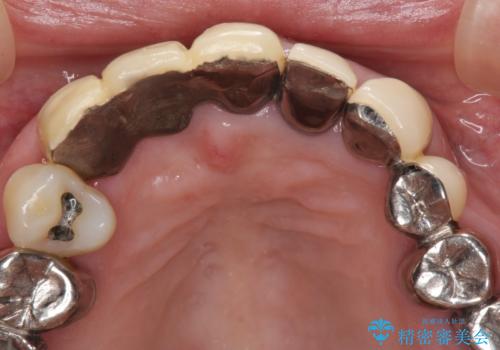

着色が著しい前歯のブリッジをオールセラミックできれいに

- 保険診療の前歯のブリッジが、形態も色も不自然で気になるとのことで来院された患者様です。

神経の抜かれている土台の歯は根管治療を行った上で、オールセラミックブリッジにより補綴することとしました。